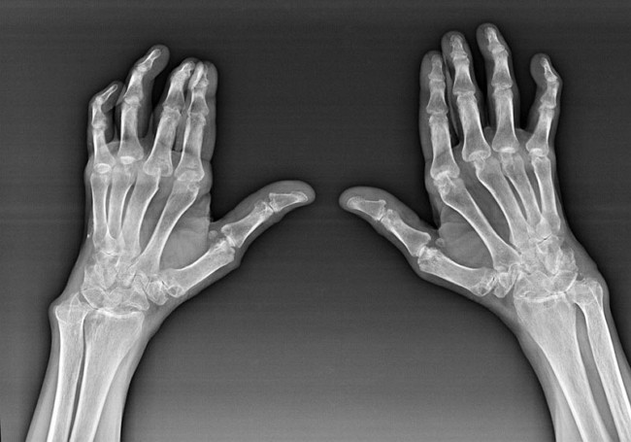

Reumatoidinis artritas

Reumatoidinis artritas yra liga, kai žmogaus imuninė sistema kenkia paties organizmo audiniams. Kitaip tariant, reumatoidinis artritas yra autoimuninė patologija. Ši liga taip pat yra sisteminė, nes su ja paveikta daug audinių (Raumenys, sąnariai, indai ir kt.) ir organai (Širdis, inkstai, plaučiai ir kt.) kūne.

Nepaisant to, kad reumatoidinis artritas yra sisteminė liga, kuriai po IT, sąnariai kenčia, o kitų audinių ir organų pažeidimas yra fone. Dėl šios ligos gali būti paveikta beveik visų rūšių šepetėlių sąnarių (riešutos, riešo driekos, metakarpal-falanx, tarpfalanx sąnariai). Pažeidimas paprastai yra simetriškas (Tie. Paveikti tie patys sąnariai) ant abiejų rankų, lydimas patinimo, pažeistų sąnarių skausmo. Ryte, pakeliant iš lovos, yra šiek tiek sustingstančių paveiktų sąnarių, kurie gali trukti apie 1 valandą, o paskui išnykti be pėdsakų.

Gana dažnai esant reumatiniam artritui šalia paveiktų šepetėlių sąnarių (Dažniau pian-falanx, tarp-falanx sąnariai) Atsiranda reumatoidiniai mazgeliai. Jie yra suapvalinta formacija, esanti po oda. Ant teptuko šie formacijos dažniausiai atsiranda ant nugaros. Palpacijos metu jie yra tankūs, neaktyvūs, neskausmingi. Jų skaičius gali skirtis.